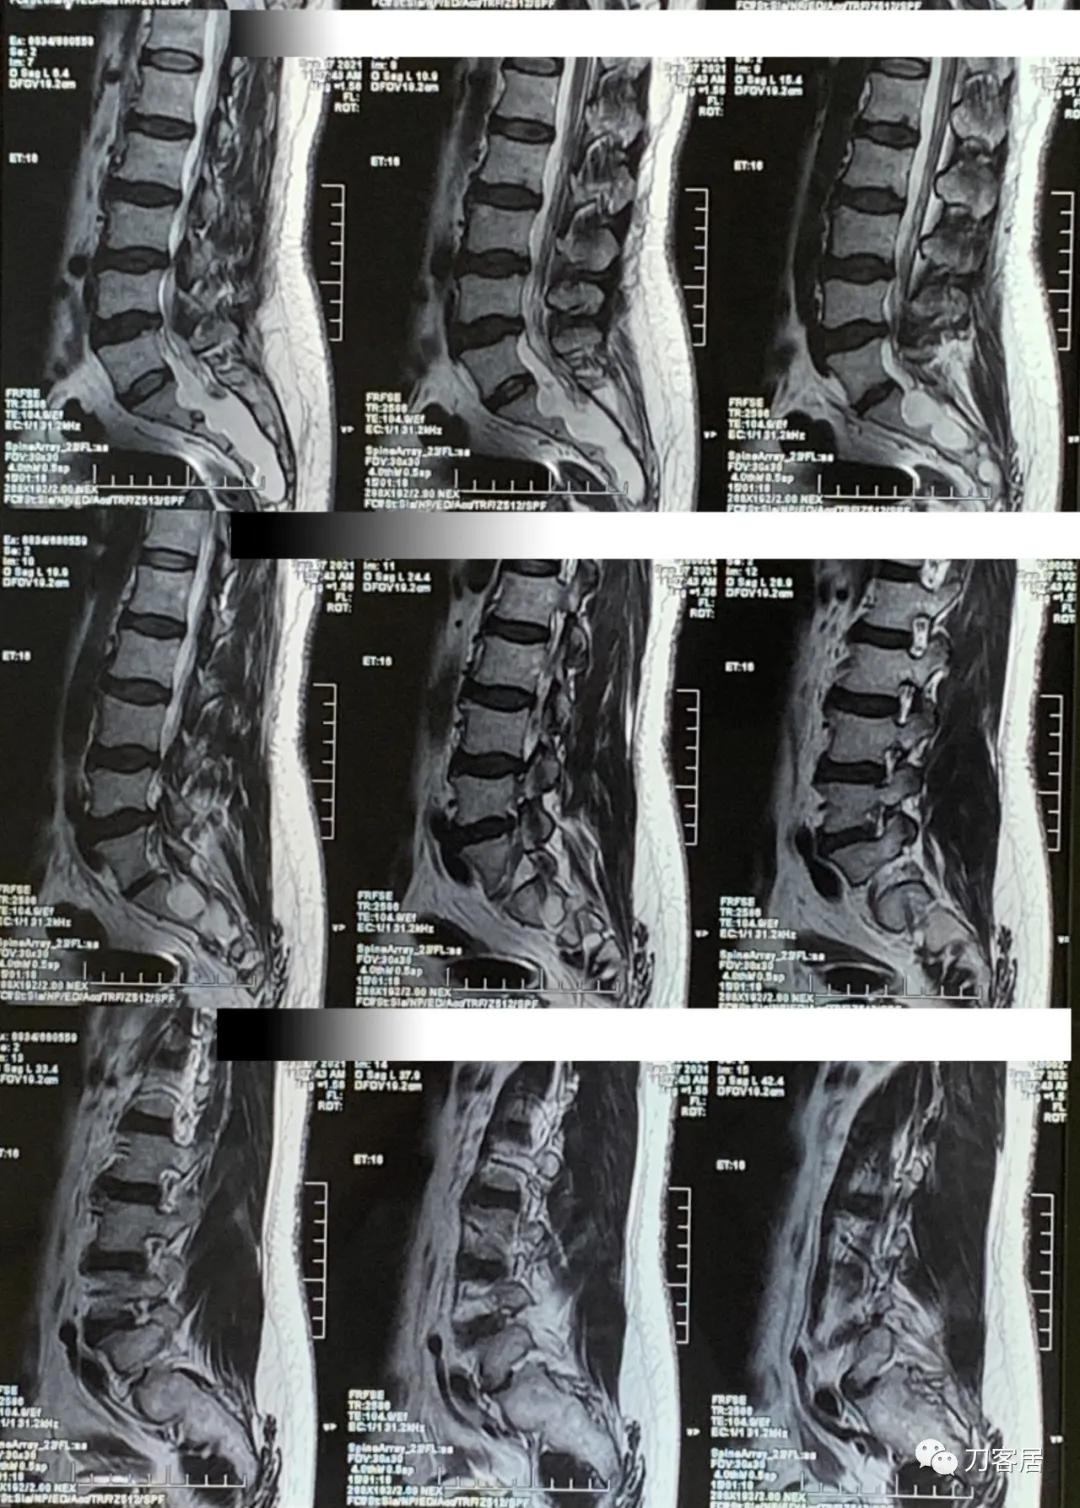

图2. 20210907西安国际医学中心腰椎MRI矢状面T2相扫描,提示腰3-4,腰4-5椎间盘突出,椎管狭窄,但似乎没那么严重,骶管囊肿,范围较大。从骶1以远都可看到。

图3. 20210907西安国际医学中心腰椎MRI矢状面T2相扫描,提示腰3-4,腰4-5椎间盘突出,椎管狭窄,但似乎没那么严重,骶管囊肿,范围较大。从骶1以远都可看到。

图4. 20210907西安国际医学中心腰椎MRI矢状面T2相扫描,提示腰3-4,腰4-5椎间盘突出,椎管狭窄,但似乎没那么严重,骶管囊肿,范围较大。从骶1以远都可看到。